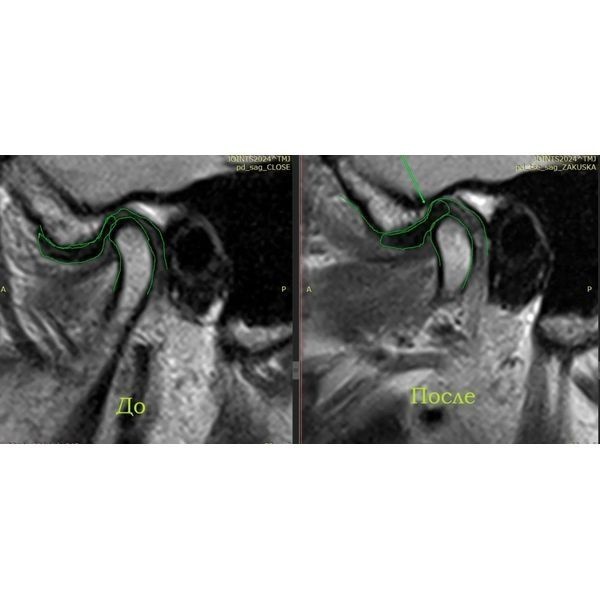

МРТ левого сустава выявила:

- вентромедиальное смещение суставного диска с частичной редукцией — диск смещён вперёд и немного внутрь (медиально), при открывании рта он частично возвращается на место;

- компрессионный тип установки головки мыщелкового отростка — головка нижней челюсти сильно прижата к суставной ямке;

- гипермобильность головок суставных отростков — головки нижней челюсти избыточно подвижны;

- дистрофические изменения диска;

- остеоартроз ВНЧС 1-й степени по Kellgren.

При моделировании будущих зубов использовались данные аксиографии: угол суставного пути (наклон ската суставной ямки), переднюю направляющую (угол наклона центральных зубов), угол окклюзионной плоскости по сфере Монсона (высота боковых зубов). После провели примерку будущих конструкций в полости рта. Когда всё согласовали (женщина скорректировала эстетические параметры — размер и форму), конструкции зафиксировали на пару месяцев и сделали контрольное МРТ. Она показала расширение суставной щели и более корректное положение суставной головки слева.